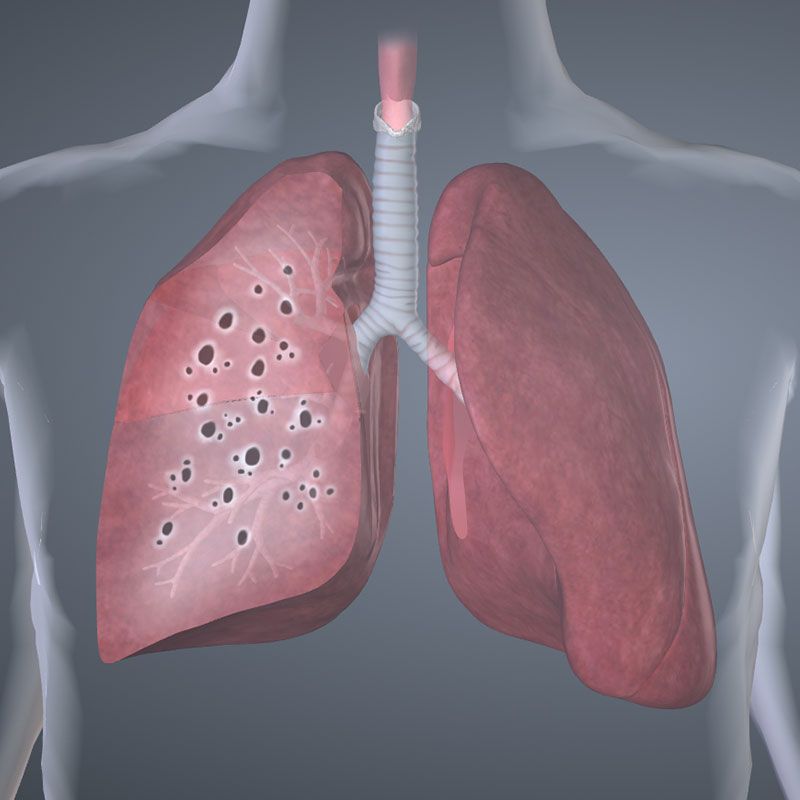

U hạt (Sarcoidosis)

18/02/2019

Những điều cần biết về bệnh U hạt